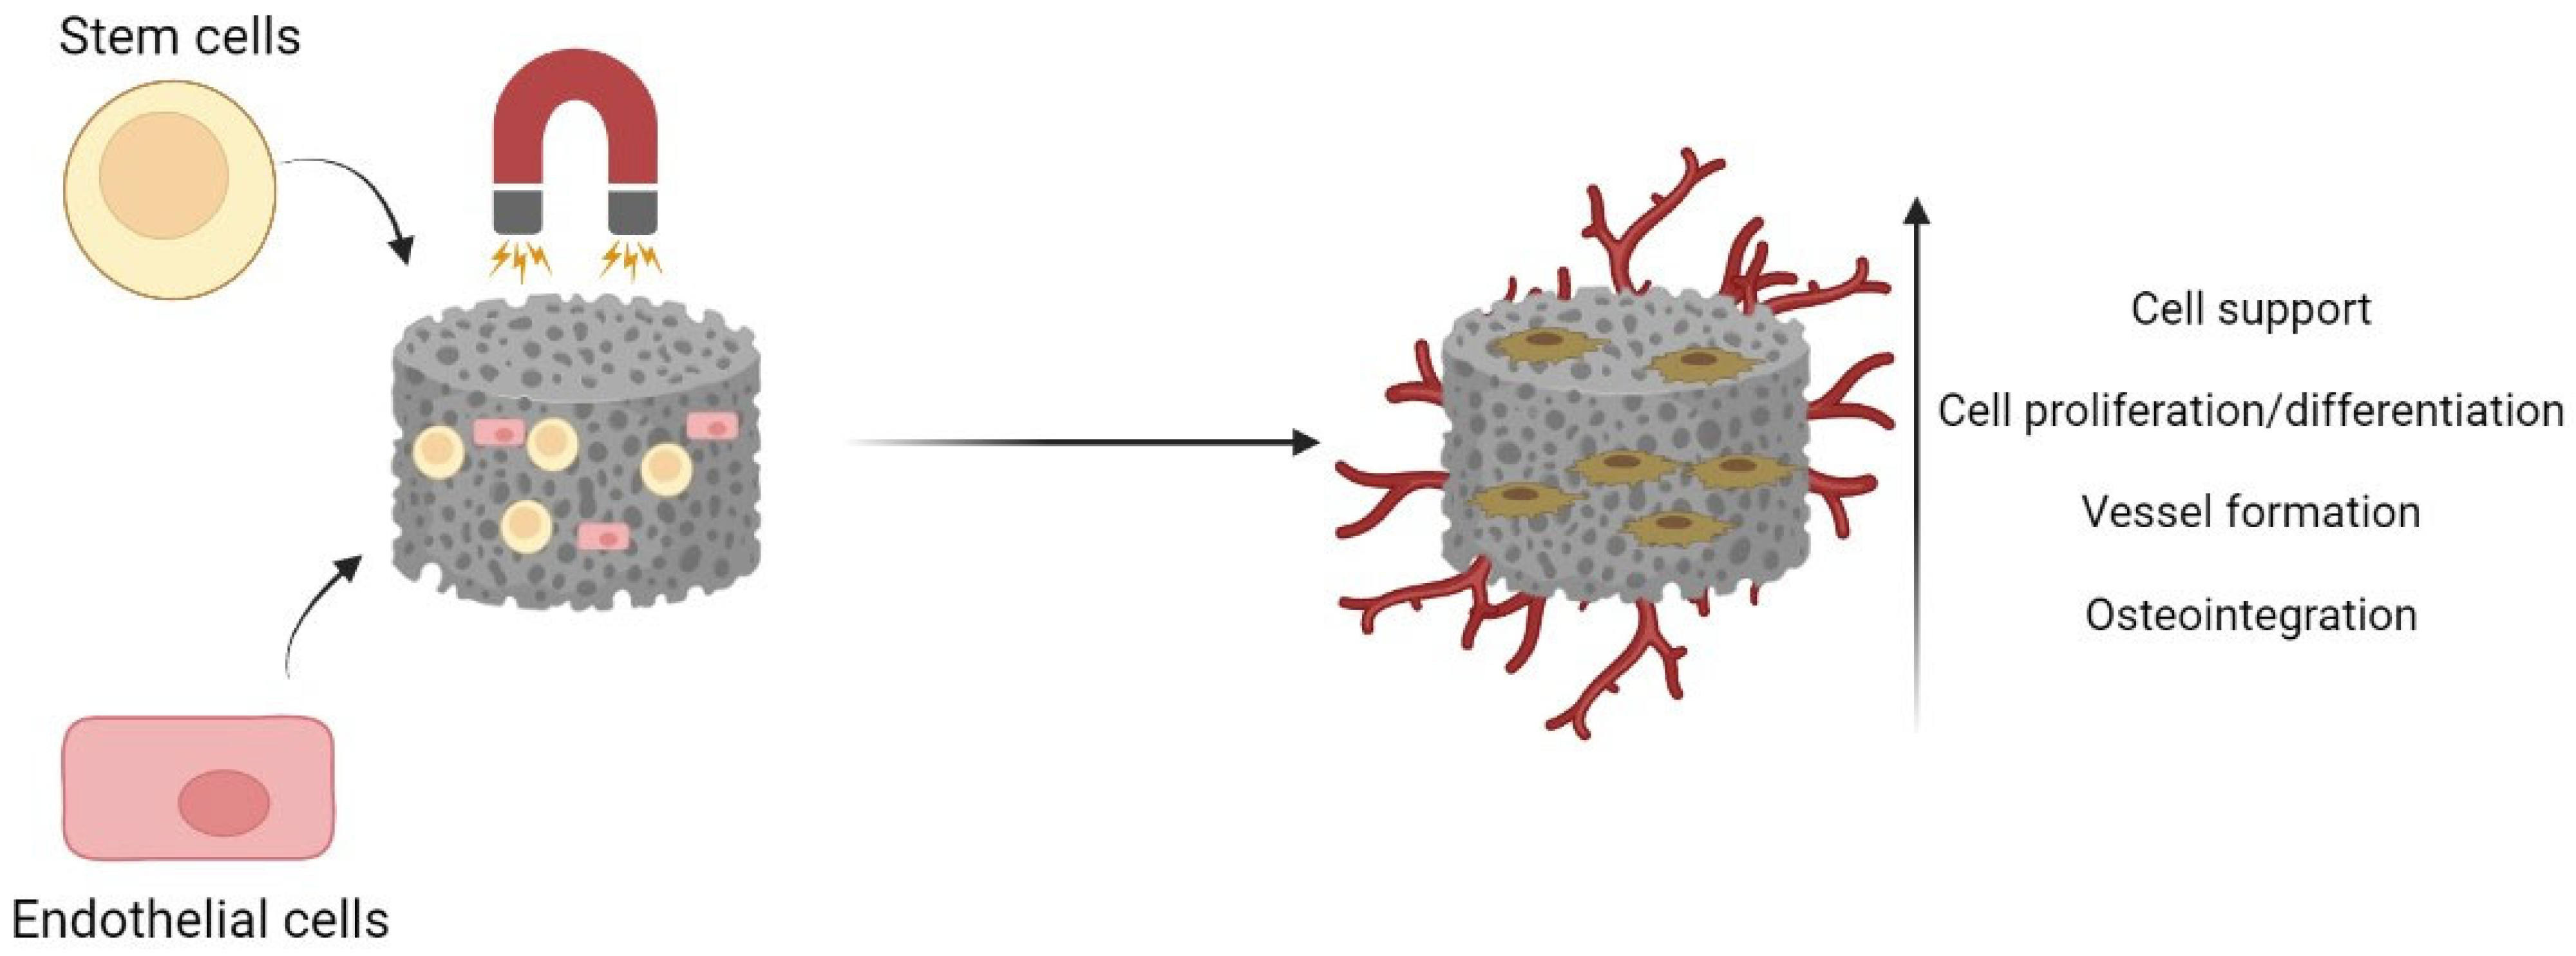

4. Magnetic Scaffolds in Bone Tissue Engineering

4.1. Production Methods of Magnetic Bone Scaffolds

4.2. Influence of Magnetic Scaffolds on Bone Regeneration

4.3. Influence of Magnetic Scaffolds on Angiogenesis